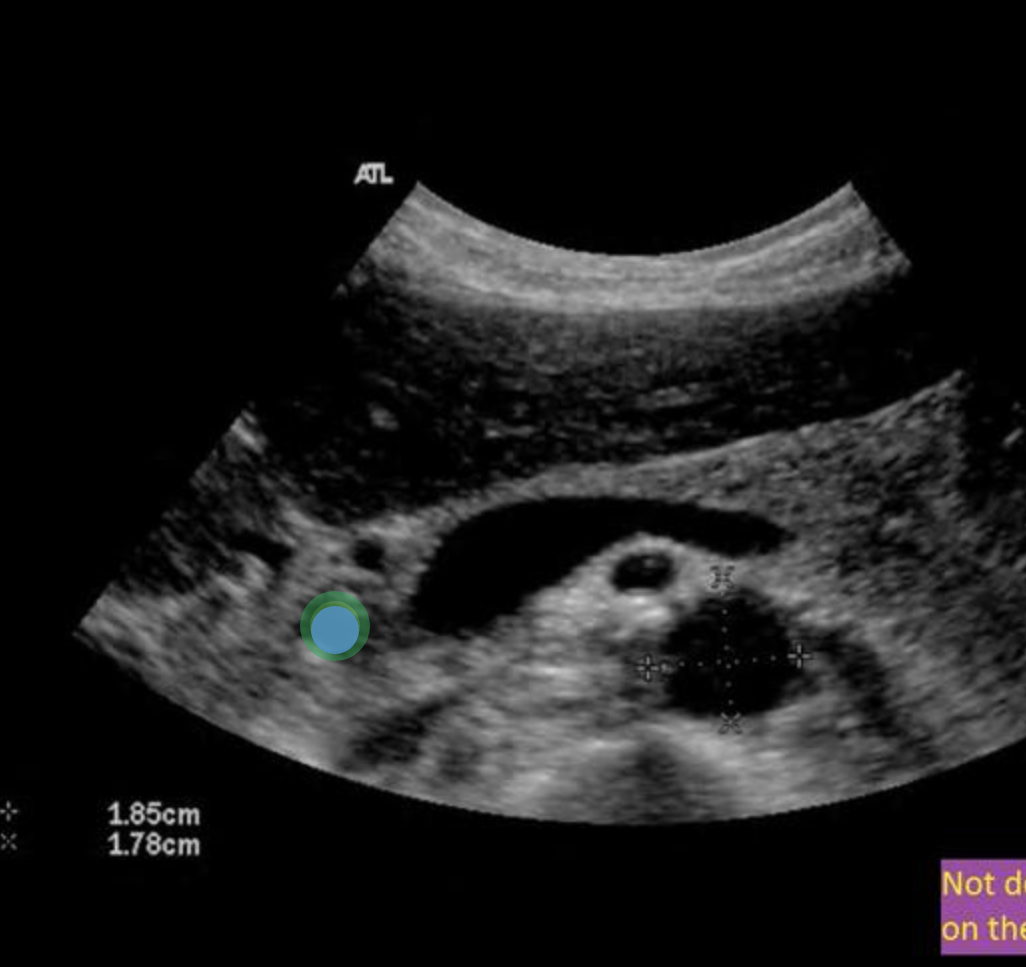

During an abdominal ultrasound, a 4mm circular anechoic structure is identified at the posterior portion of the pancreas head. Color flow is not identified in the structure. What is it?

common bile duct

Use your mouse to place your cursor over the superior mesenteric vein and click to mark the vessel. If the vessel is not demonstrated on the image, mark the purple box that says "Not demonstrated on the image".